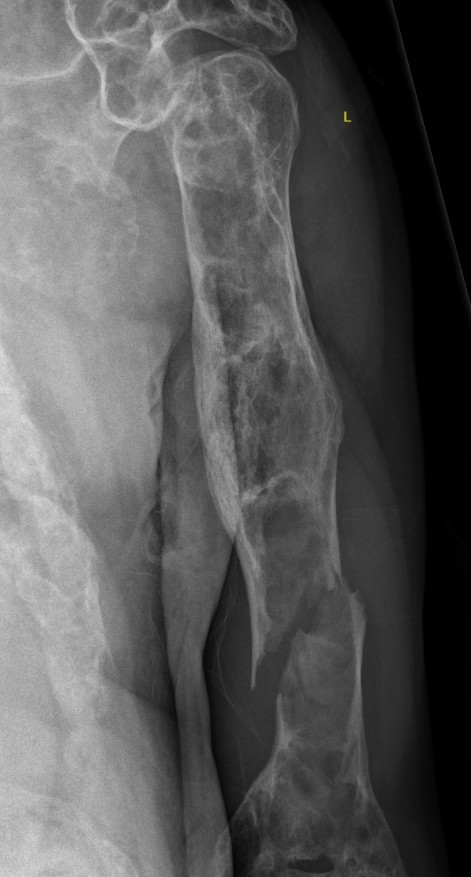

Intramedullary lucent diaphyseal lesion with 'ground glass appearance'

- thinned, slightly bulged cortex

- ± endosteal scalloping

- may have angular deformity / bowing

Coxa vara and Shepherd's Crook deformity of proximal femur

- Shepherd's Crook - anterior bowing of femur

Sabre tibia

Pathological fracture